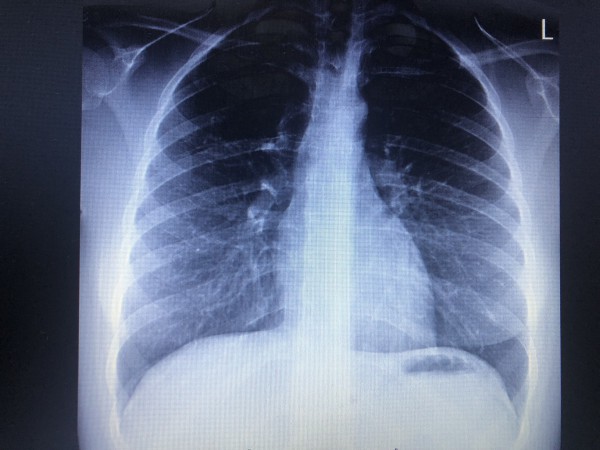

Hej, od paru miesiecy odczuwam uczucie kulki w prawym płucu, ból promieniuje do głowy potem do łopatki a z łopatki do ręki(wszystko prawa strona). Mam zrobione RTG i chciałabym was poprosić o interpretacje bo do wyników od lekarza nie wytrzymam. Dziękuje.